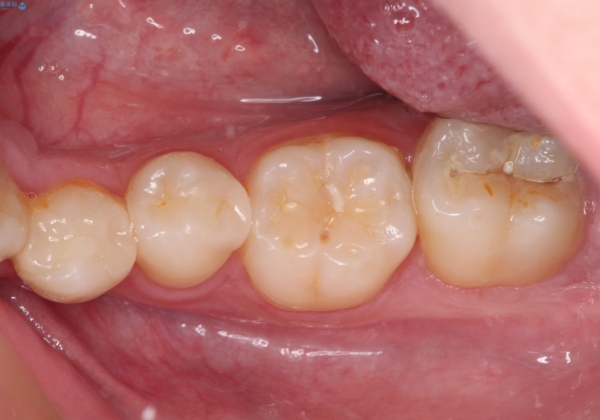

詰め物が欠けた セラミックインレーによる修復

- 以前治療した詰め物が欠けてしまったことを主訴として来院した患者様です。

食べ物がはさまったり、冷たいものがしみるといった症状がみられました。

むし歯の染め出し液と拡大鏡を用いて、むし歯がないことを確認し、

セラミックインレーにて修復することとしました。